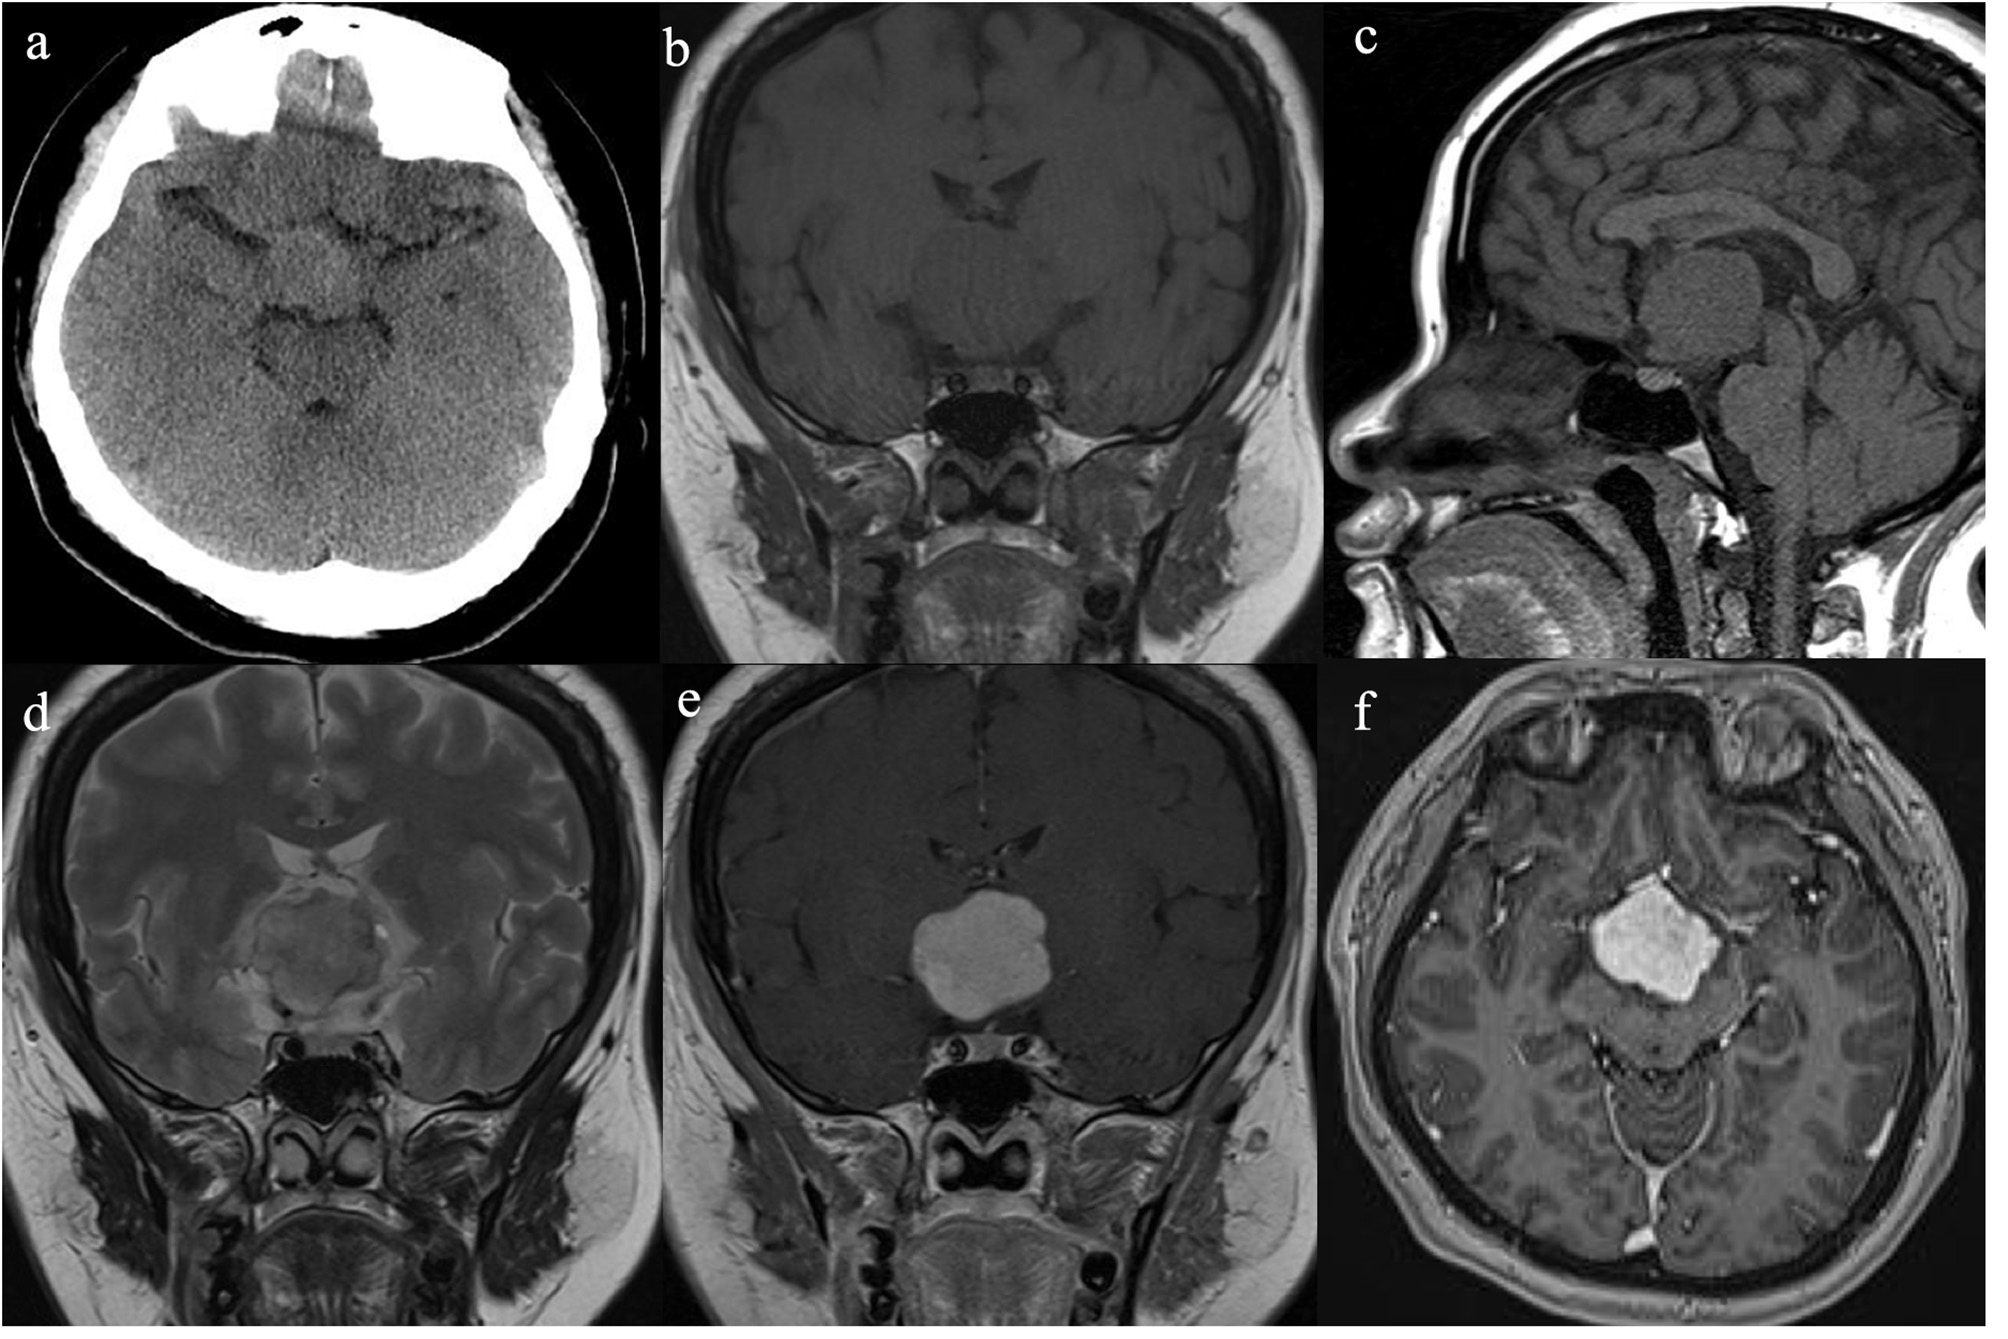

She had no history of smoking and alcohol consumption and any significant past medical history. She also had no family history of cancer. She had normal moods and cognition and no obvious memory disturbance. Visual problems and galactorrhea were excluded. The general physical and specific neurological examinations were unremarkable. Her weight and height were 105 kg and 156 cm, respectively, and she had a body mass index of 43.15 kg/m2 and blood pressure of 138/88 mmHg. Hormonal, serological, and urinary examinations indicated no abnormality; select hormone levels are shown in Table 1. Chest radiography indicated no suspected lung mass or pathology. Brain non-contrast computed tomography showed a well-circumscribed, irregularly ovoid tumor in the third ventricle, which was slightly hyperdense (Figure 1a). Magnetic resonance imaging (MRI) showed a well-defined ovoid mass measuring 4.5 × 3.3 × 4.1 cm. The tumor demonstrated intermediate signal intensity on T1-weighted images (Figures 1b,c) and slightly high and high signal intensity on T2-weighted images (Figure 1d). Post-contrast enhancement images indicated prominent homogeneous enhancement (Figures 1e,f). The lesion was separated from the pituitary. Hydrocephalus was not detected. Clinical symptoms and radiological data were discussed at a multidisciplinary team meeting. The tumor was considered to have arisen from the third ventricle and was therefore unlikely to be either a craniopharyngioma or a pituitary adenoma. After discussions with the patient and her family, they opted for conservative treatment, and we decided on subtotal resection (STR).

Figure 1

Radiological evaluation of CG preoperatively. A none-contrast CT scan showed a slightly hyper-dense mass located at suprasellar and the third ventricle (a). The tumor was slightly hypo-intense on Coronal and Sagittal T1WI (b,c) and slightly hyper-intense on Coronal T2WI (d). Post-contrast (gadolinium-enhanced) Coronal and Axial MRI (e,f) show prominent homogeneous enhancement.

Enhanced MRI of the brain with gadolinium is reported to be the best diagnostic imaging tool for the evaluation of CG. CG is typically a well-circumscribed, round or oval-shaped tumor. CGs have isointensity on T1-weighted images and slight hyperintensity on T2-weighted images (10–12). After gadolinium injection, they have strong homogenous enhancement, and cystic changes and necrosis may be present, but calcifications are rare (8, 11–13). Our patient's imaging findings were consistent with those previouly described, and the tumor was separated from the pituitary, probably arising from the third ventricle, so we thought this lesion might be CG rather than craniopharyngioma or pituitary adenoma. Therefore, surgery was performed via the right modified transpterional port approach. MRI not only helps to diagnose CG but also suggests the most suitable surgical approach.